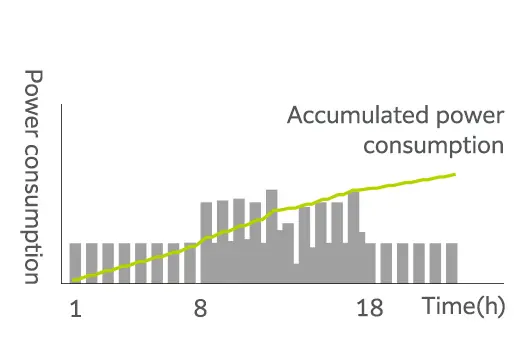

Gereksiz güç tüketimini en aza indirme

Genel olarak, süper iletken MRG sistemi yüksek işletme maliyetiyle bilinir. Bu maliyet esas olarak süper iletkenliği korumak için gerekli olan soğutma sisteminin yüksek güç tüketiminden kaynaklanır. ECHELON Smart Plus, kullanılmadığı dönemlerde soğutma sistemini belirli bir süre durdurabilen bir enerji tasarrufu işlevi olan SmartECO ile donatılmıştır. Bu işlev, helyum kaybına sebep olmadan güç tüketimini etkili bir şekilde azaltır. Dahası, bu süreler boyunca soğutma sisteminden gelen ısı emisyonu azaldıkça, ısı dağıtma ünitesinin güç tüketimi de azalır.

Daha az ısı tahliyesi olan bir MRG ünitesine sahip kompakt bir tarama odası, muayene ve ekipman odalarının iklimlendirme gereksinimlerini de azaltır. Isı tahliyesinin azaltılmasıyla birlikte enerji tasarrufu işlevi çalıştırma maliyetlerini %17*3 oranında azaltabilir